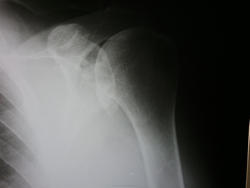

Это может быть оторванным фрагментом передне-нижней части суставной впадины лопатки.Но ! Качество- хреновое, надо-бы переснять.

Конкремент в нижнем завороте плечевого сустава.

Я в-общем то как и Фил, думаю что это похоже на оторванный фрагмент гленоидальной впадины. больше ничего в голову не приходит..

Вначале порекомендовал бы сделать дополнительные проекции. В дополнение к перелому можно предположить наличие обызвествившихся мягких тканей, сухожилий или сумок. А судя по теням на фоне суставной впадины, то и "костные мыши".

думается, тут травматический частичный отрыв гленоида. Пациентка из поля зрения вышла, увы.